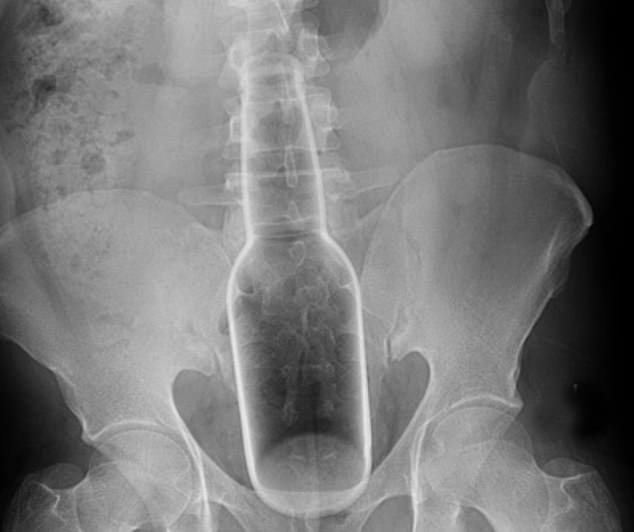

9. Ένα μπουκάλι ποτού